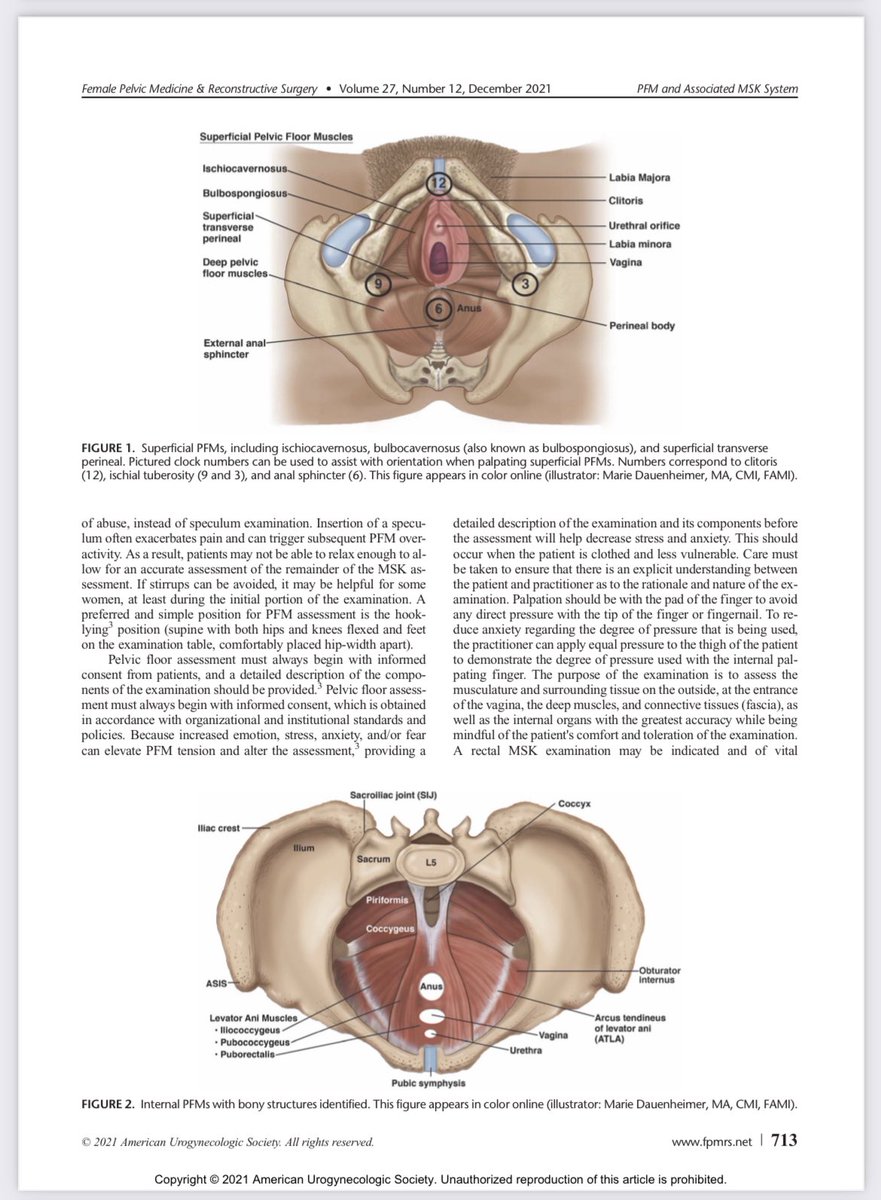

To be bookmarked! A stellar multidisciplinary team (PT, PM&R, Urogyn) authored this new AUGS guidance on the examination of the pelvic floor and associated musculoskeletal system. @FPMRSJournal Jerry Lowder Emily L. Whitcomb, MD, MAS augs.org/assets/1/6/Ass…

Disfunció del sòl pelvià: prevenció i maneig no quirúrgic. Guia NICE buff.ly/3DDzinQ SBGO @comaresapm Asoc balear comares COLFISIOBALEAR RHB_HUSLL